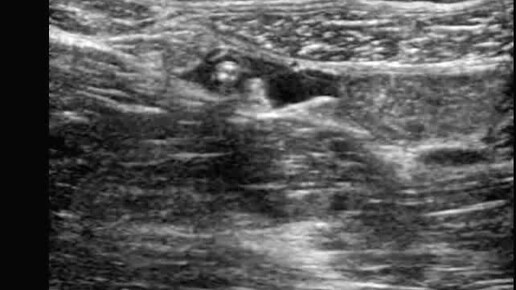

Ультразвуковые находки от врача УЗД Зорина Я.П.